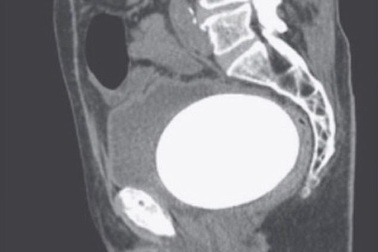

Nam thiếu niên mang cục sỏi khổng lồ ở bàng quangNhập viện trong tình trạng tiểu khó, thường xuyên đau vùng bụng dưới kèm theo sốt nhẹ, bệnh nhân được bác sĩ xác định có cục sỏi khổng lồ nằm trong bàng quang.